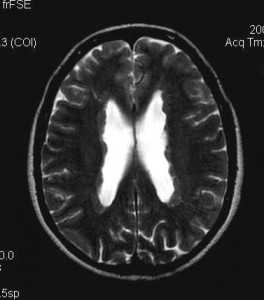

Стволовой инсульт, в отличие от опухолей, обычно не дает масс-эффекта. При МРТ головного мозга очаг гиперинтенсивен на Т2-взвешенных МРТ и не сопровождается вздутием ствола.

МРТ головного мозга. Аксиальная Т2-взвешенная МРТ. Стволовой инсульт.